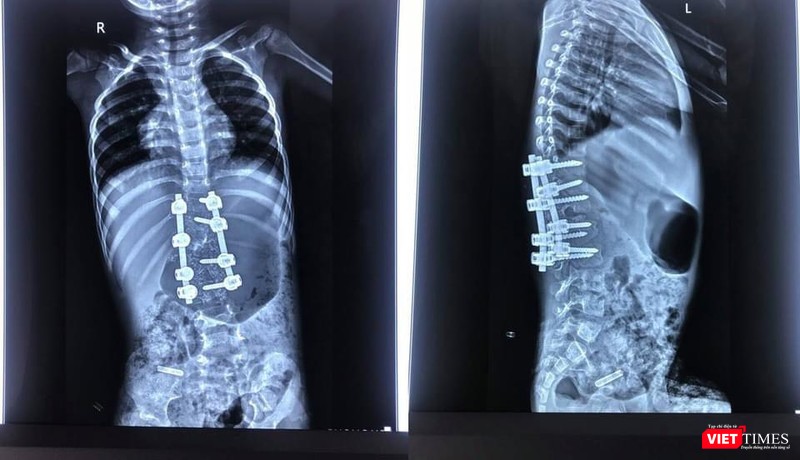

Bác sĩ cho biết sau phẫu thuật biến dạng được nắn chỉnh rất tốt |

Để nắn chỉnh được tối đa biến dạng vẹo này thì cần phải cắt được phần thân đốt dị tật và cố định cột sống tương đối dài từ T10-L3. Như vậy, có nhiều vấn đề trong phẫu thuật như: khả năng mất máu lớn trong mổ, nguy cơ làm tổn thương tủy - rễ thần kinh có thể dẫn đến liệt chân, bộc lộ vết mổ rộng, bắt nhiều vít vào cột sống trên bệnh nhân nhi, 12 kg.

Ngoài ra, không có loại vít cột sống dành riêng cho trẻ em, các mũ vít khá lớn với bệnh nhân nhi.

Ca phẫu thuật diễn ra gần 4 tiếng, lượng máu mất nhiều, cần phải truyền 300ml khối hồng cầu và 150ml huyết tương tươi, cân bằng toan hóa máu sau truyền máu, điều chỉnh tất cả các chỉ số xét nghiệm và chỉ số sinh tồn về trong giới hạn.

Sau mổ, bệnh nhi đã được nắn chỉnh tốt biến dạng cong vẹo cột sống, không có tổn thương thần kinh. Bệnh nhi hồi phục thuận lợi, hai chân vận động bình thường. Bé đang tập ngồi và đi lại được, tiểu tự chủ.

Hình ảnh X-quang sau mổ cho thấy biến dạng được nắn chỉnh rất tốt, còn giữ được chức năng 3 đĩa đệm cuối cùng của cột sống thắt lưng. Ca phẫu thuật thành công mang lại một dấu mốc với khoa Chấn thương - Chỉnh hình Cột sống (B1-D) và khoa Gây mê hồi sức (B5) của BV 108, mở ra cơ hội cho nhiều bệnh nhi khác.